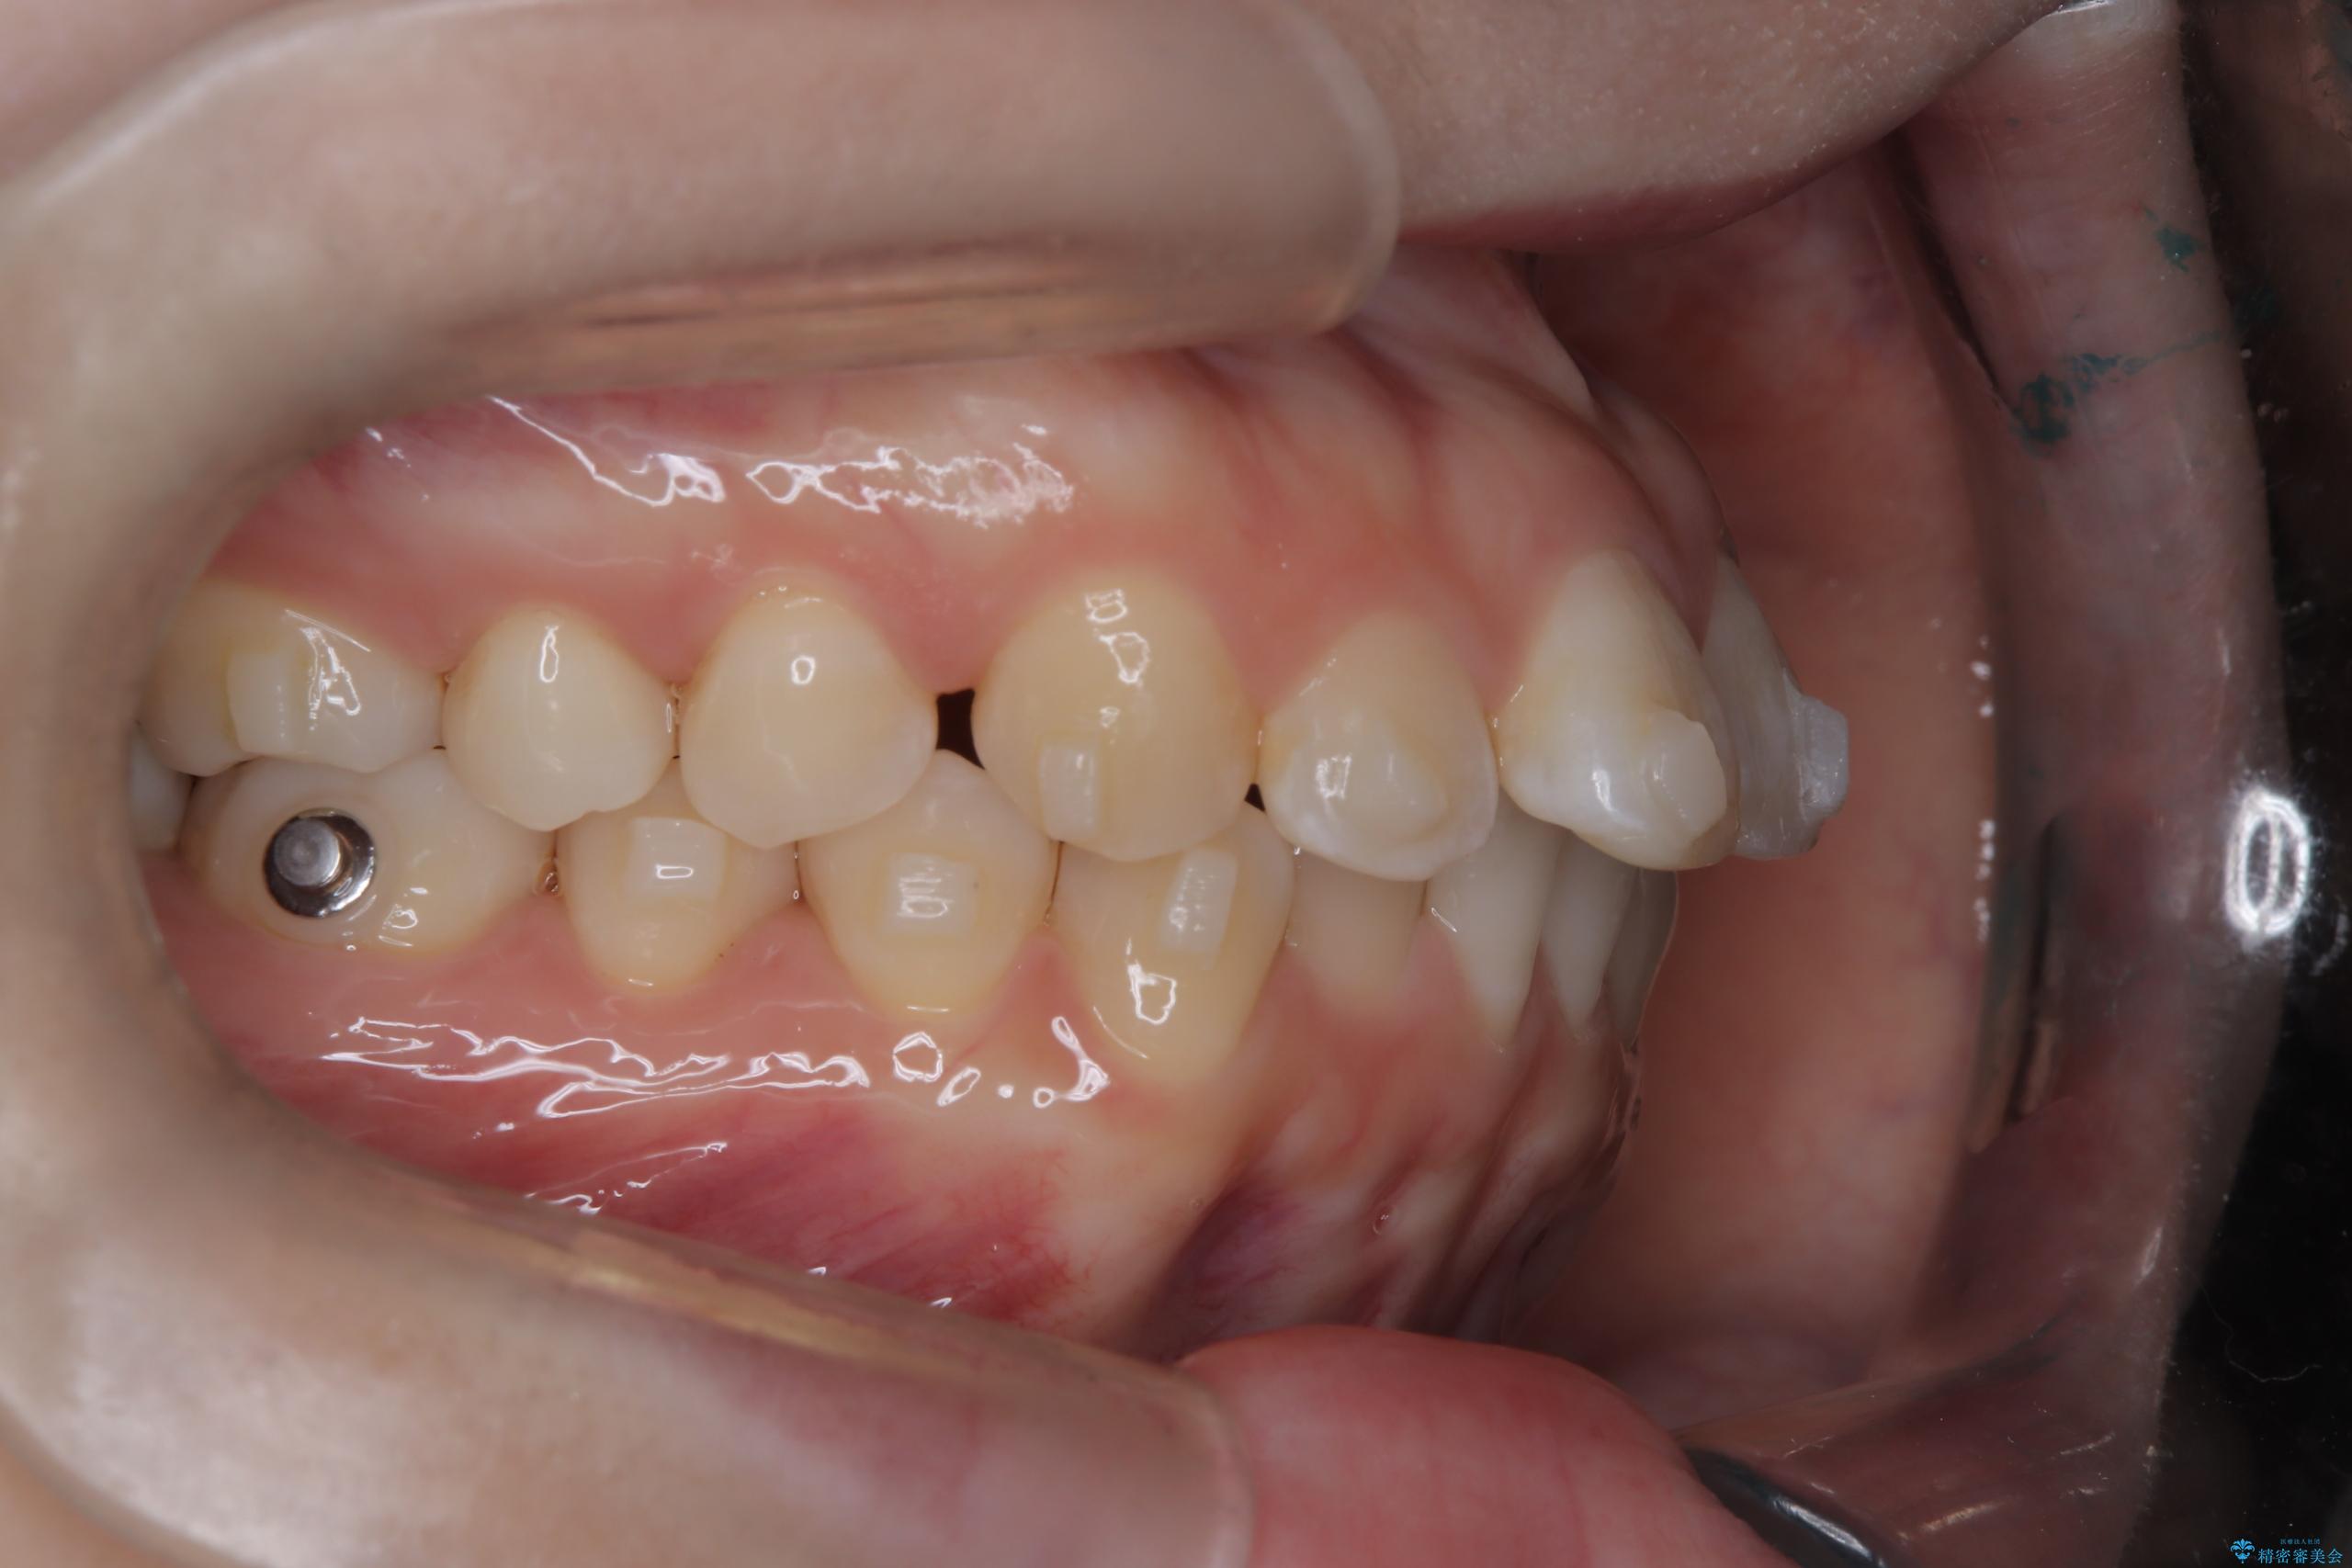

- 前歯のデコボコ(叢生)を気にされてご来院されました。精密な検査の結果、歯が並ぶスペースが不足していることが判明。患者様のご希望から、透明で目立ちにくいインビザライン(マウスピース矯正)による治療計画を立案しました。抜歯を避け、奥歯全体を奥へ動かす遠心移動という方法でスペースを確保し、前歯の叢生を解消することを目指します。

今回の矯正治療では、透明なマウスピース型の装置インビザラインを使用しました。この装置は取り外し可能で、日常生活で目立ちません。治療は、緻密に計算された計画に基づき、段階的に作製されたマウスピースを交換していくことで、奥歯から順に全体を後方へ移動させる遠心移動を実施。これにより、前歯を並べるための十分なスペースが確保され、デコボコが解消されました。抜歯することなく、機能的にも審美的にも整った美しい歯並びを獲得していただけました。